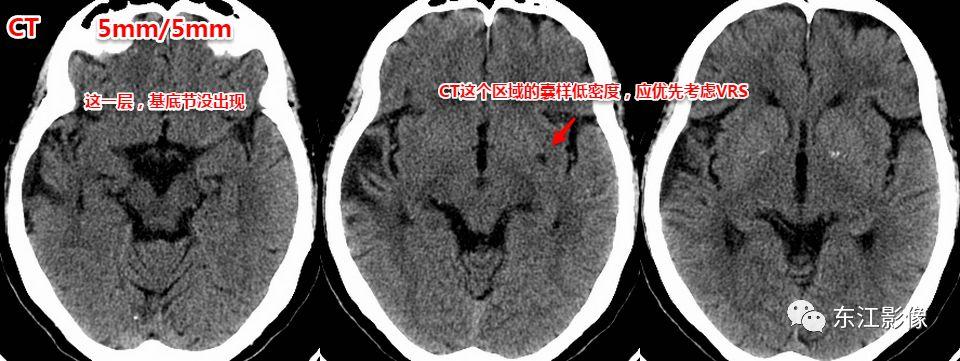

前穿质区VRS经典CT、MRI影像。

- 常见部位:前穿质区,外囊区,额顶叶皮层下,中脑。——务必熟记!

- 其他部位:丘脑,颞枕叶皮层下,侧脑室周围白质,小脑。